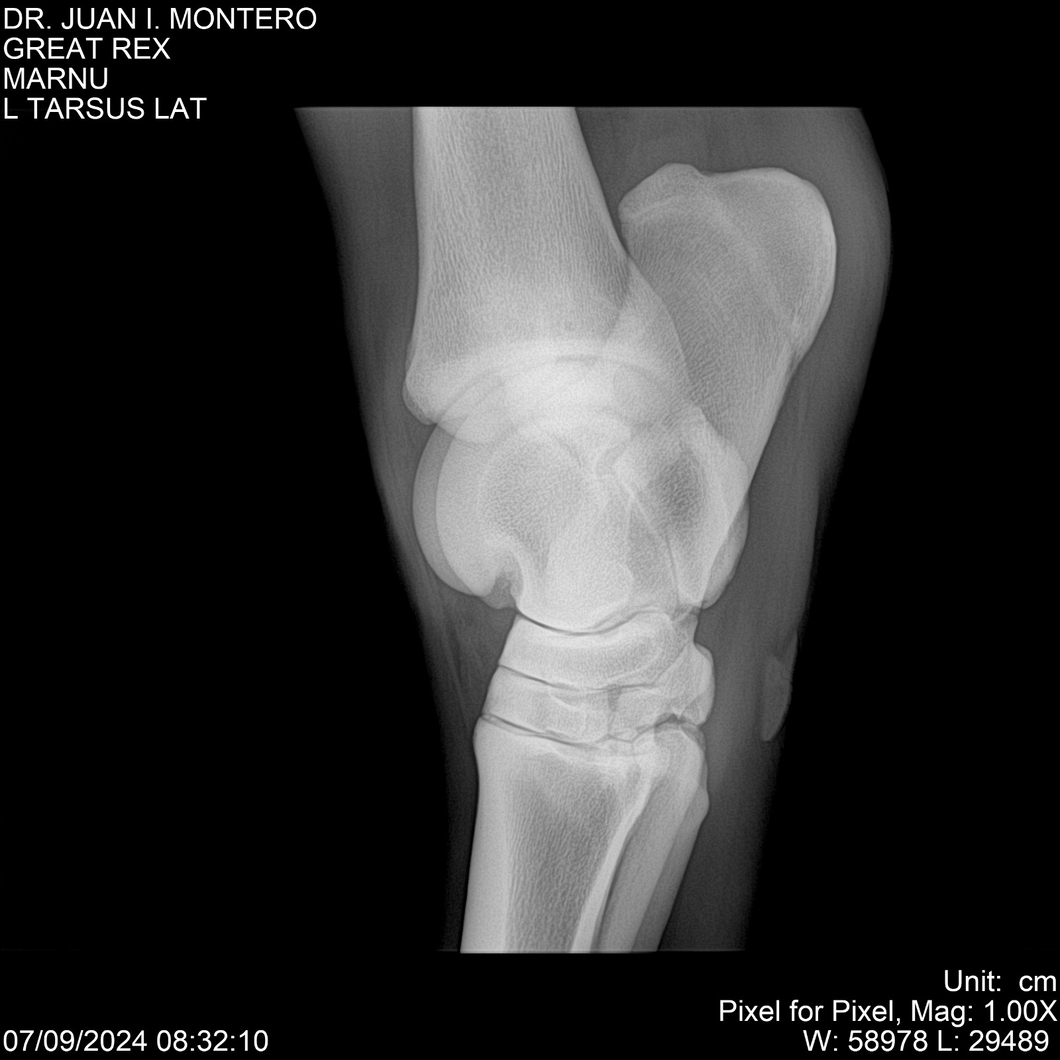

LOTE 4, GREAT REX Lote Anterior Volver al remate Lote Siguiente Ficha Contacto Montevideo - Ficha del Lote Identificador: #282518 Categoría: Yeguarizos Montevideo - 66 Visualizaciones ClicData Contacto Empresa: Abelenda N. R., Walter Hugo Nombre*: Teléfono* : E-mail* : Mensaje Enviar Registrese gratis Este contenido Exclusivo está disponible sólo para usuarios registrados Ingresar